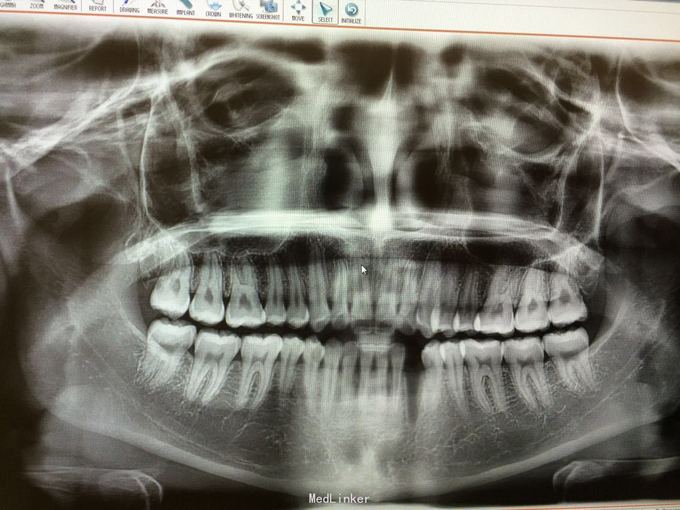

D3完全脱位,伤口血凝块已经凝固,颊侧牙龈钝性撕裂。D2D4无叩痛和松动。脱落牙齿牙体硬组织完好,牙周膜干裂,牙体上有纸屑和食物残渣,根尖有牙髓组织呈黑红色。

D3牙脱位 D3体外根管治疗后垫底充填,盐水和双氧水浸泡后,刮尽牙根的牙周膜后放置盐水和庆大霉素液中15分钟。局麻下刮除牙槽窝内血凝块至流鲜血后盐水和庆大霉素交替冲洗,明胶海绵拭干牙槽窝,浸泡好的牙体植入牙槽窝内并复位,舌侧树脂牙周夹板固定D123456,牙周上派丽奥。随诊

1天后复诊,3天后复诊,7天后复诊,一个月后复诊,3个月后复诊。1个半月后复诊未发现牙周有较大吸收和炎症感染。